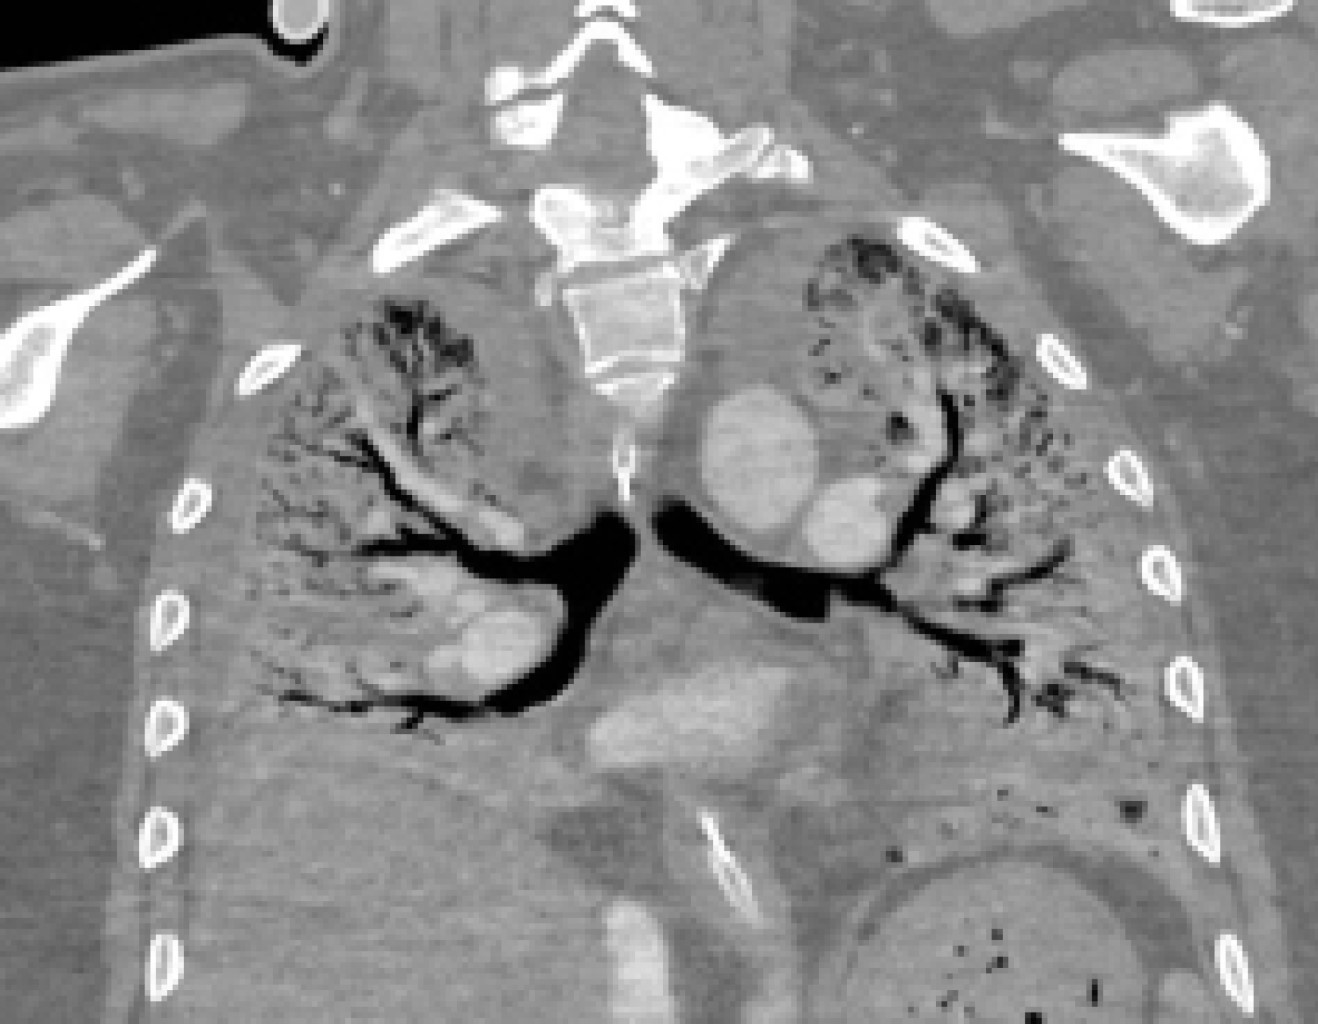

El paciente salió a terapia intensiva y las primeras 24 horas tuvo un gasto elevado por las sondas torácicas que hizo necesario reintervenirlo para control de sangrado. A las 72 horas posoperatorias el ECMO fue retirado. Se inició el proceso de rehabilitación física y respiratoria con el retiro lento de la ventilación mecánica. La inmunosupresión utilizada consistió en: tacrolimus, mofetil micofenolato y prednisona. El paciente recibió profilaxis bacteriana para citomegalovirus, hongos (con anfotericina nebulizada) y para Pneumocystis jirovecii. La evolución clínica fue paulatinamente hacia la mejoría hasta que fue decanulado de traqueostomía en el día 30 posoperatorio y fue dado de alta deambulando en el día 41 posoperatorio (Figuras 4 y 5).

Figura 4